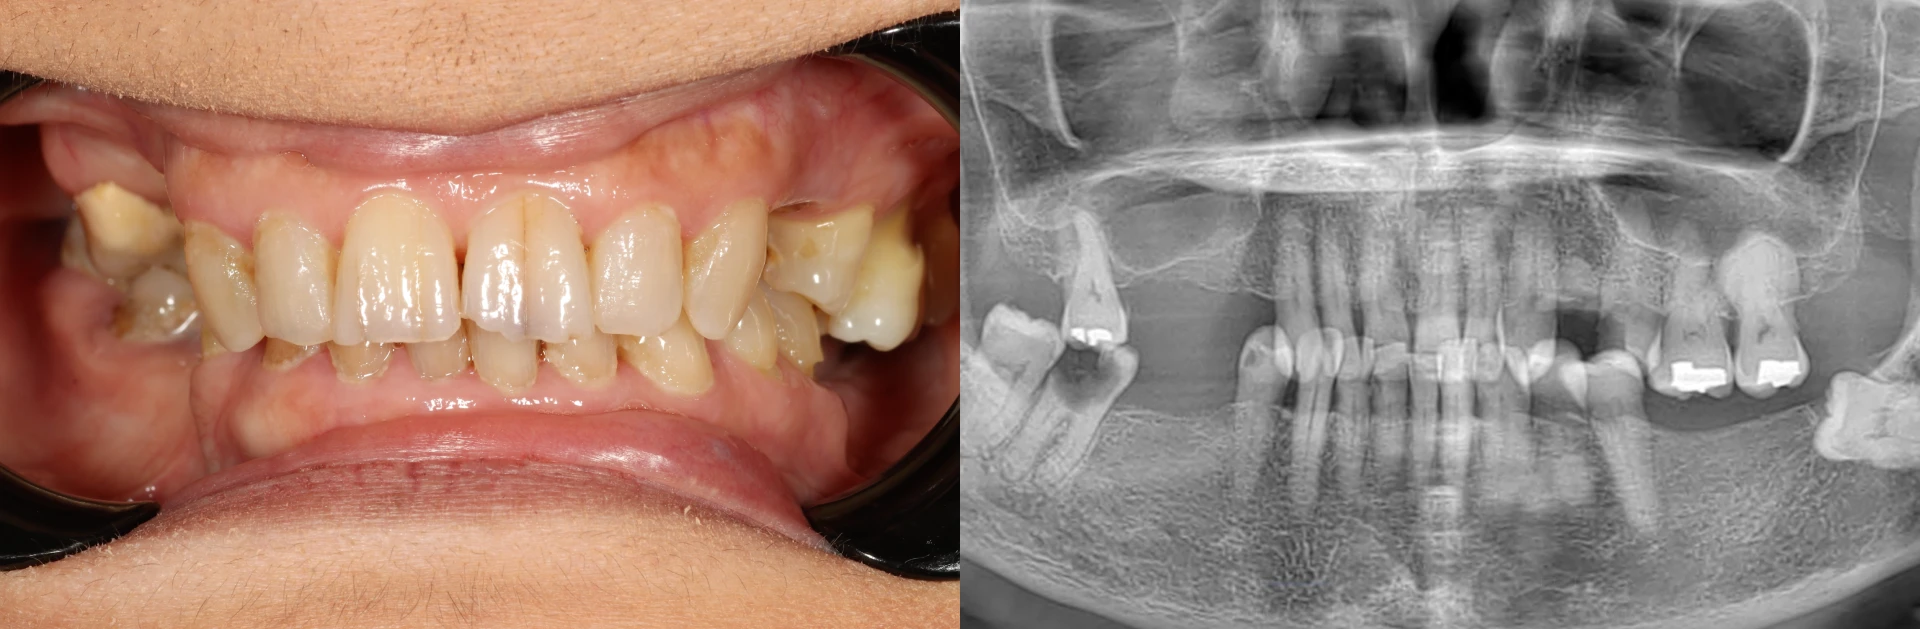

An examination revealed several complex issues that are common in cases where a full mouth solution is needed:

A patient's smile before all on 4 dental implants, including a panoramic x-ray showing missing teeth and decay.

• Missing Back Teeth: Like many patients, she had lost her back molars first. This forced her to chew with her front teeth, which are not designed for the heavy forces of grinding food, leading to a cascade of other problems.

• Damage to Front Teeth: The excessive pressure on her front teeth led to chips, visible cracks, and significant wear that compromised their strength and appearance.

• Widespread Cavities: Large cavities were present in several of her remaining teeth. These teeth were too decayed to be saved with fillings or crowns, making them unsalvageable.

• Hyper-Eruption: Some of her upper teeth, with no opposing lower teeth to bite against, had drifted down into the empty space. This dental issue makes the teeth non-functional and eliminates the room needed to place new teeth on the bottom arch.

• Aesthetic Concerns: She was unhappy with the gray and yellow staining, visible plaque and calculus buildup, and the overall look of her smile, which made her hesitant to smile fully.